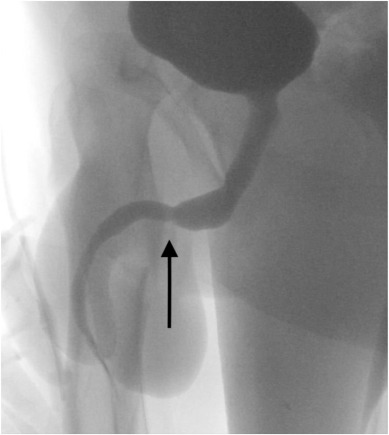

El equipo médico intentó remover el cable a través de una cistoscopia rígida y una uretrotomía óptica, pero ambos intentos fallaron debido al enredo. Por lo tanto, se necesitó cirugía para extraer el objeto extraño.

En términos más simples, los médicos hicieron una incisión penoescrotal longitudinal y realizaron una disección cuidadosa para extraer el cable del adolescente. Los extremos del cable se retiraron con éxito a través del meato urinario externo, y el paciente se recuperó bien después de la cirugía.